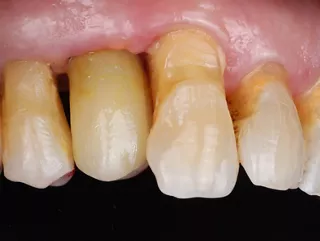

Treatment results

Phase V: At delivery of the definitive restoration, peri-implant tissues around tooth 15 were healthy and stable, with a harmonious emergence profile, adequate buccal thickness, and no signs of inflammation, bleeding, or recession. Continuous use of the Healfit® SH abutment from surgery through impression preserved soft-tissue contours by minimizing disconnections (Fig 6a & b).

Radiographs confirmed stable crestal bone levels without peri-implant radiolucency (Fig 10). The 3Y-TZP zirconia crown exhibited light centric contacts and smooth lateral guidance, integrating well into occlusion without discomfort. Aesthetically, the crown blended naturally with adjacent teeth, and the patient reported high satisfaction (Fig 12a & b). Maintenance visits showed improved plaque control compared to baseline, supporting long-term stability and prognosis.

12a. 12b. Intraoral view of the final prosthesis in place: X-Base® abutment supporting a 3Y-TZP crown at position 15.

12a

12b